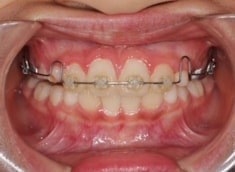

治療開始から6ヶ月後

治療開始から6ヶ月で反対咬合の解消は達成されておりますが、これで治ったわけではなく、上顎の劣成長を改善しなければならないので、ここからしっかりとフェイスマスクを使用していただきます。